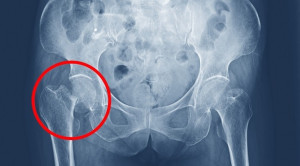

• Manajemen Nyeri Fraktur Collum Femur – Blok Saraf Perifer vs Blok Neuroaxial

Manajemen Nyeri Fraktur Collum Femur – Blok Saraf Perifer vs Blok Neuroaxial

Manajemen nyeri fraktur collum femur dapat dilakukan dengan blok saraf perifer, blok neuroaxial, pemberian obat antiinflamasi nonsteroid atau OAINS, maupun pemberian opioid....(Baca Selengkapnya)

• Keuntungan Blok Saraf Perifer pada Pasien dengan Fraktur Panggul

Keuntungan Blok Saraf Perifer pada Pasien dengan Fraktur Panggul

Penggunaan blok saraf perifer pada pasien dengan fraktur panggul atau fraktur leher femur diduga mengurangi kebutuhan opioid baik sebelum, saat, maupun sesudah...(Baca Selengkapnya)

• Red Flags Nyeri Panggul

Red Flags Nyeri Panggul

Adanya red flags atau tanda bahaya nyeri panggul menandakan kondisi yang perlu ditangani segera, seperti fraktur patologis atau septic arthritis. Nyeri panggul...(Baca Selengkapnya)